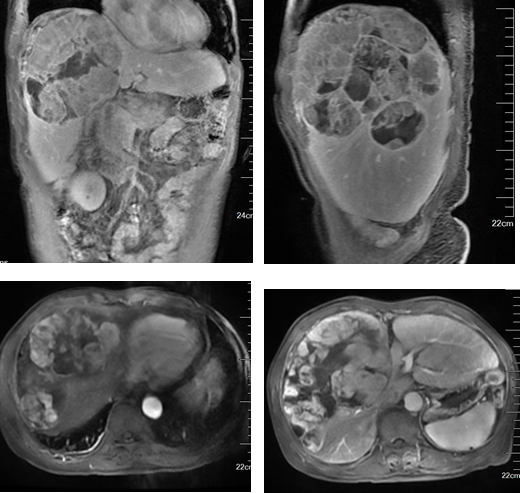

胸部CT未见明确异常,上腹部MRI影像表现:肝脏形态不规则,肝裂增宽,肝实质内可见多发软组织肿块影,呈稍长/稍短T1、稍长T2异常信号,增强扫描动脉期病灶明显、欠均匀强化,门脉期及平衡期强化减低,延迟期见假包膜强化,病灶部分融合,病灶大者11.5cmX18.1cmX14.8cm,肝门及右侧心膈角区可见多发增大淋巴结,大者短径约5mm。

影像诊断:肝内多发占位,考虑原发性肝癌可能性大,并病灶破裂,肝包膜下积血、积液;肝门部及右侧心膈角区多发增大淋巴结;肝硬化、腹水;肝段下腔静脉狭窄。